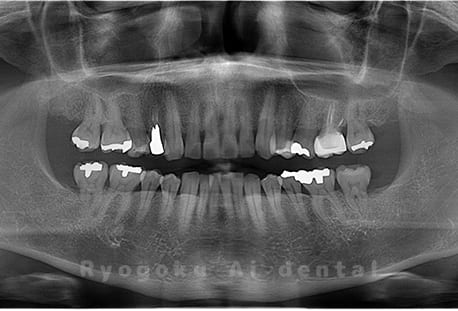

Case02

-

- 原因

- 下顎の水平埋伏智歯

- 治療内容

- 下顎の水平埋伏智歯を抜歯

<リスク・副作用>

手術後は痛み、腫れ、痺れなどの副作用が生じる場合があります。